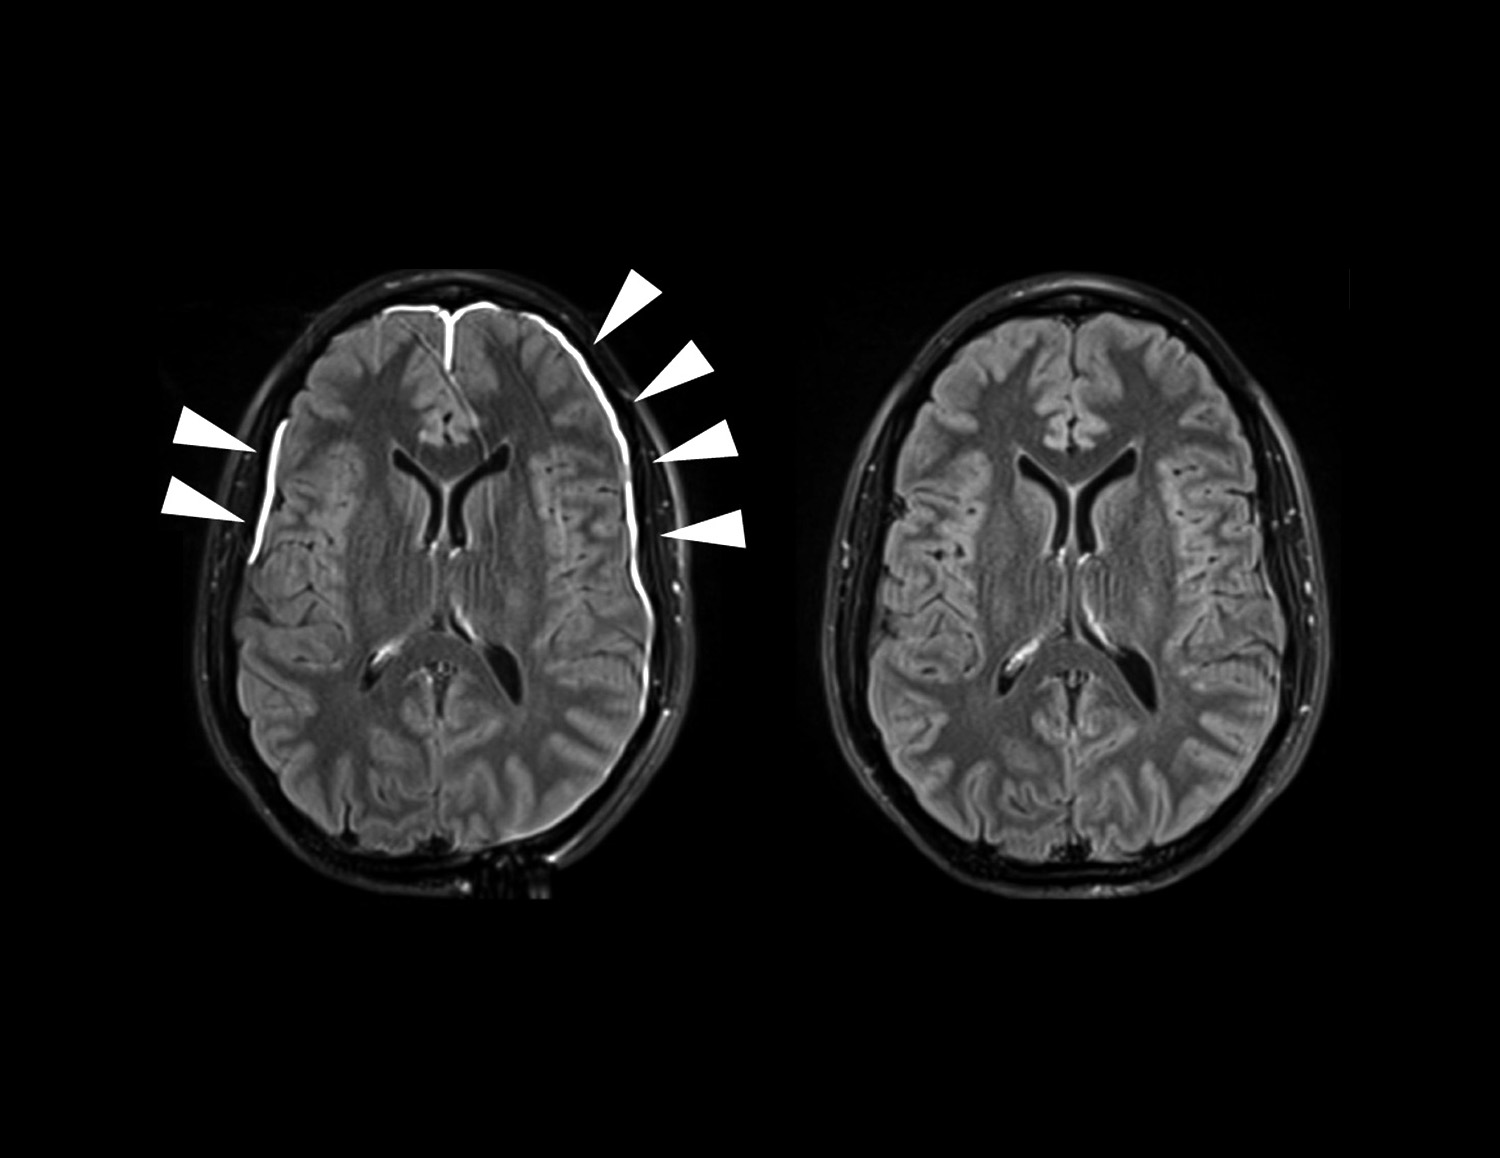

NIH Scientists Watch The Brain s Lining Heal After A Head Injury

https://www.nih.gov/sites/default/files/news-events/news-releases/2018/20180416-hu-tbi.jpg